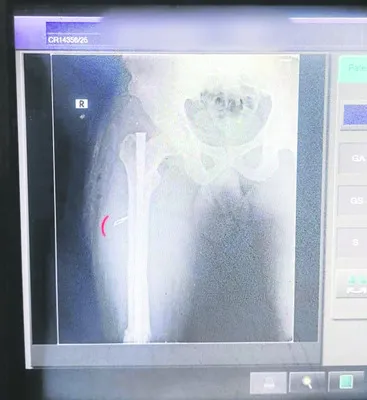

తుని: స్థానిక ఏరియా ఆసుపత్రి నిర్లక్ష్య వైఖరి రోగులను ఆందోళనకు గురి చేస్తోంది. ఓ వ్యక్తి కాలులో అమర్చిన ఐరన్రాడ్డు బోల్టు తొలగించి సిజేరియన్ బ్లేడును కాలులోనే ఉంచి కుట్టు వేసిన ఘటన శుక్రవారం చోటుచేసుకుంది. వివరాల్లోకి వెళితే.. మండలం ఎస్.అన్నవరం పంచాయతీ రామకృష్ణానగరానికి చెందిన వ్యక్తి ఏడాదిన్నర క్రితం కాలుకు గాయం కావడంతో ఏరియా ఆసుపత్రిలో శస్త్ర చికిత్స చేయించుకున్నాడు. గాయం బలమైంది కావడంతో అప్పట్లో ఐరన్రాడ్డు సైతం అమర్చారు. ఐరన్ రాడ్డు బోల్టును తొలగిస్తే త్వరగా సర్దుకోవచ్చు అనే ఆలోచనతో శుక్రవారం ఏరియా ఆసుపత్రికి వెళ్లాడు. ఆసుపత్రిలో సిబ్బంది ఆపరేషన్ చేసి రాడ్డు బోల్టు తొలగించారు. అయితే కాలులో సిజేరియన్ బ్లేడును ఒకటి ఉంచేసి కుట్లు వేసేశారు. ఇలా చేసారేంటని బాధితుడు సిబ్బందిని ప్రశ్నిస్తే దాడికి యత్నించారని రోగి వాపోయారు.